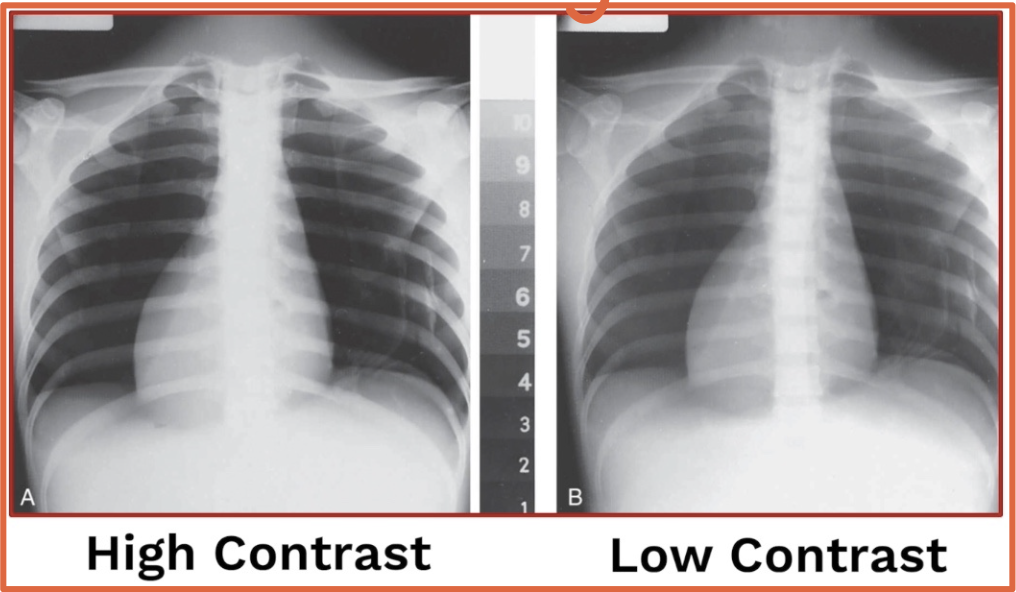

Thoracic spine → HIGH contrast & A-P

Chest x-ray → LOW contrast & P-A